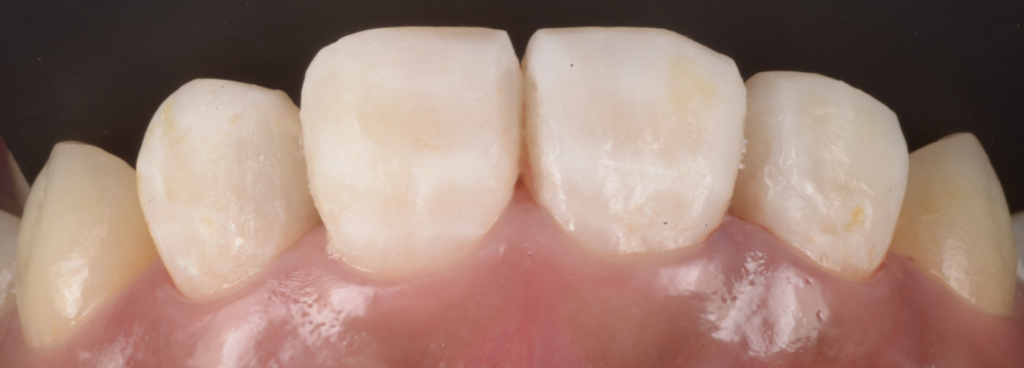

治療方針|上顎前歯部を“ダイレクトボンディングで完結”させる

今回の治療は、最終的にダイレクトボンディング(CR接着修復)で完結しました。

ただし、前歯のダイレクトは「白い材料を詰めるだけ」では成立しません。

- 審美(色・透明感・形)

- 機能(噛み合わせ、切縁の当たり)

- 再発予防(密閉、マージン精度)

この3つを同時に成立させる必要があります。

仕上げのポイント|「詰めた直後」より「数年後」を見据える

前歯の修復は、治した直後にきれいでも、マージンが荒ければ着色しやすく、再発リスクが上がります。

だからこそ当院では、

- マージンの精密な調整

- 研磨の質(プラーク付着を減らす)

- 噛み合わせの確認(切縁・側方運動の干渉)まで含めて完成度を上げます。

“きれいに見える”だけでなく、清掃性が高く、密閉が保たれ、力学的にも壊れにくい形を目指すことが、歯を守る修復です。